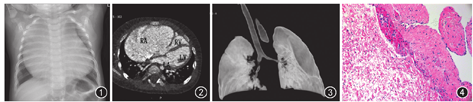

患儿 男,8个月,体重9.0 kg, 2015年11月9日因体检发现心脏杂音收住我院。体格检查显示胸骨左缘3~ 4肋间闻及4/6及收缩期杂音,心电图示房性心律,出生史、接种史及家族史无特殊。患儿生长发育稍差,易患呼吸道感染,住院期间有2次呼吸困难发作,伴口唇青紫,吸氧后好转。超声心动图检查提示右心房瘤样扩张。X线胸片所示,心影明显增大,右心缘明显向外突出(图1)。CT血管成像(CTA)示,右心房体积明显增大,约8.9 cm×5.1 cm×2.4 cm,三尖瓣环及右侧房室环结构同时受压向前下方移位,三尖瓣隔瓣及后瓣附着于右侧房室环水平,右心室腔较小,右心室形态完整,即流入道、体部、心尖部及流出道结构存在。左心房及心室大小正常,双房未见血栓影。影像诊断:右心房房壁瘤(right atrial aneurysm, RAA),伴右心室发育不良(图2)。CT仿真支气管镜显示右侧中间段支气管受压变窄(图3)。

手术及病理所见:术中见右心房极度扩张,大小约5.5 cm×3.5 cm,房壁菲薄,组织疏松,占据大部分心包腔,心脏受压,卵圆孔未闭,大小约0.3 cm。切除右心房大部分瘤变组织,保留部分接近正常的心房组织以维持心房功能,关闭卵圆孔。术后病理检查所示:右心房部分心肌壁组织,心肌细胞变性,血管扩张,部分呈纤维组织增生,伴玻璃样变性,间质小血管增生及血管周围淋巴细胞浸润,符合房壁瘤(图4)。术后复查胸片显示心脏体积明显缩小。